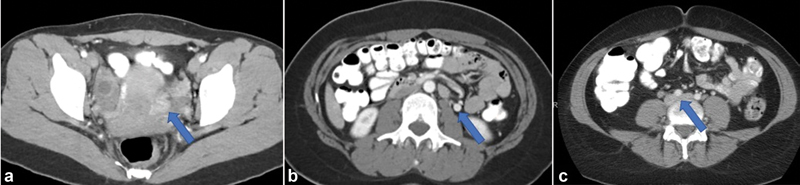

Given the typical population of patients with CPP, CT is not preferred secondary to its use of ionizing radiation and lack of time resolution. In patients who are unable to obtain authorization for a pelvic MRI, it may be useful in distinguishing PeVD from other causes of CPP based on the presence and diameter of pelvic varices. CTV may also be helpful in cases of suspected PeVD where the primary obstruction involves the CIV or external iliac vein (EIV). 42 CT may also be performed in the evaluation of these patients by other providers allowing for identification of pelvic varicosities, dilated and refluxing OVs, or iliac vein compression ( Fig. 2 ).

Fig. 2.

Contrast-enhanced CT images demonstrating ( a ) left periovarian varices (arrow), ( b ) dilated left ovarian vein with retrograde flow of contrast (arrow), and ( c ) left common iliac vein compression by the overlying right common iliac artery (arrow).